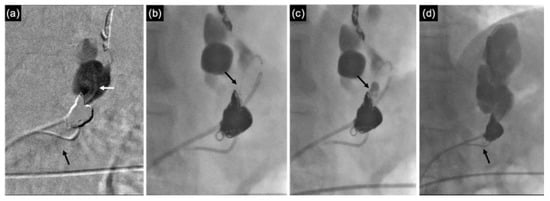

3.2.2. CARTO